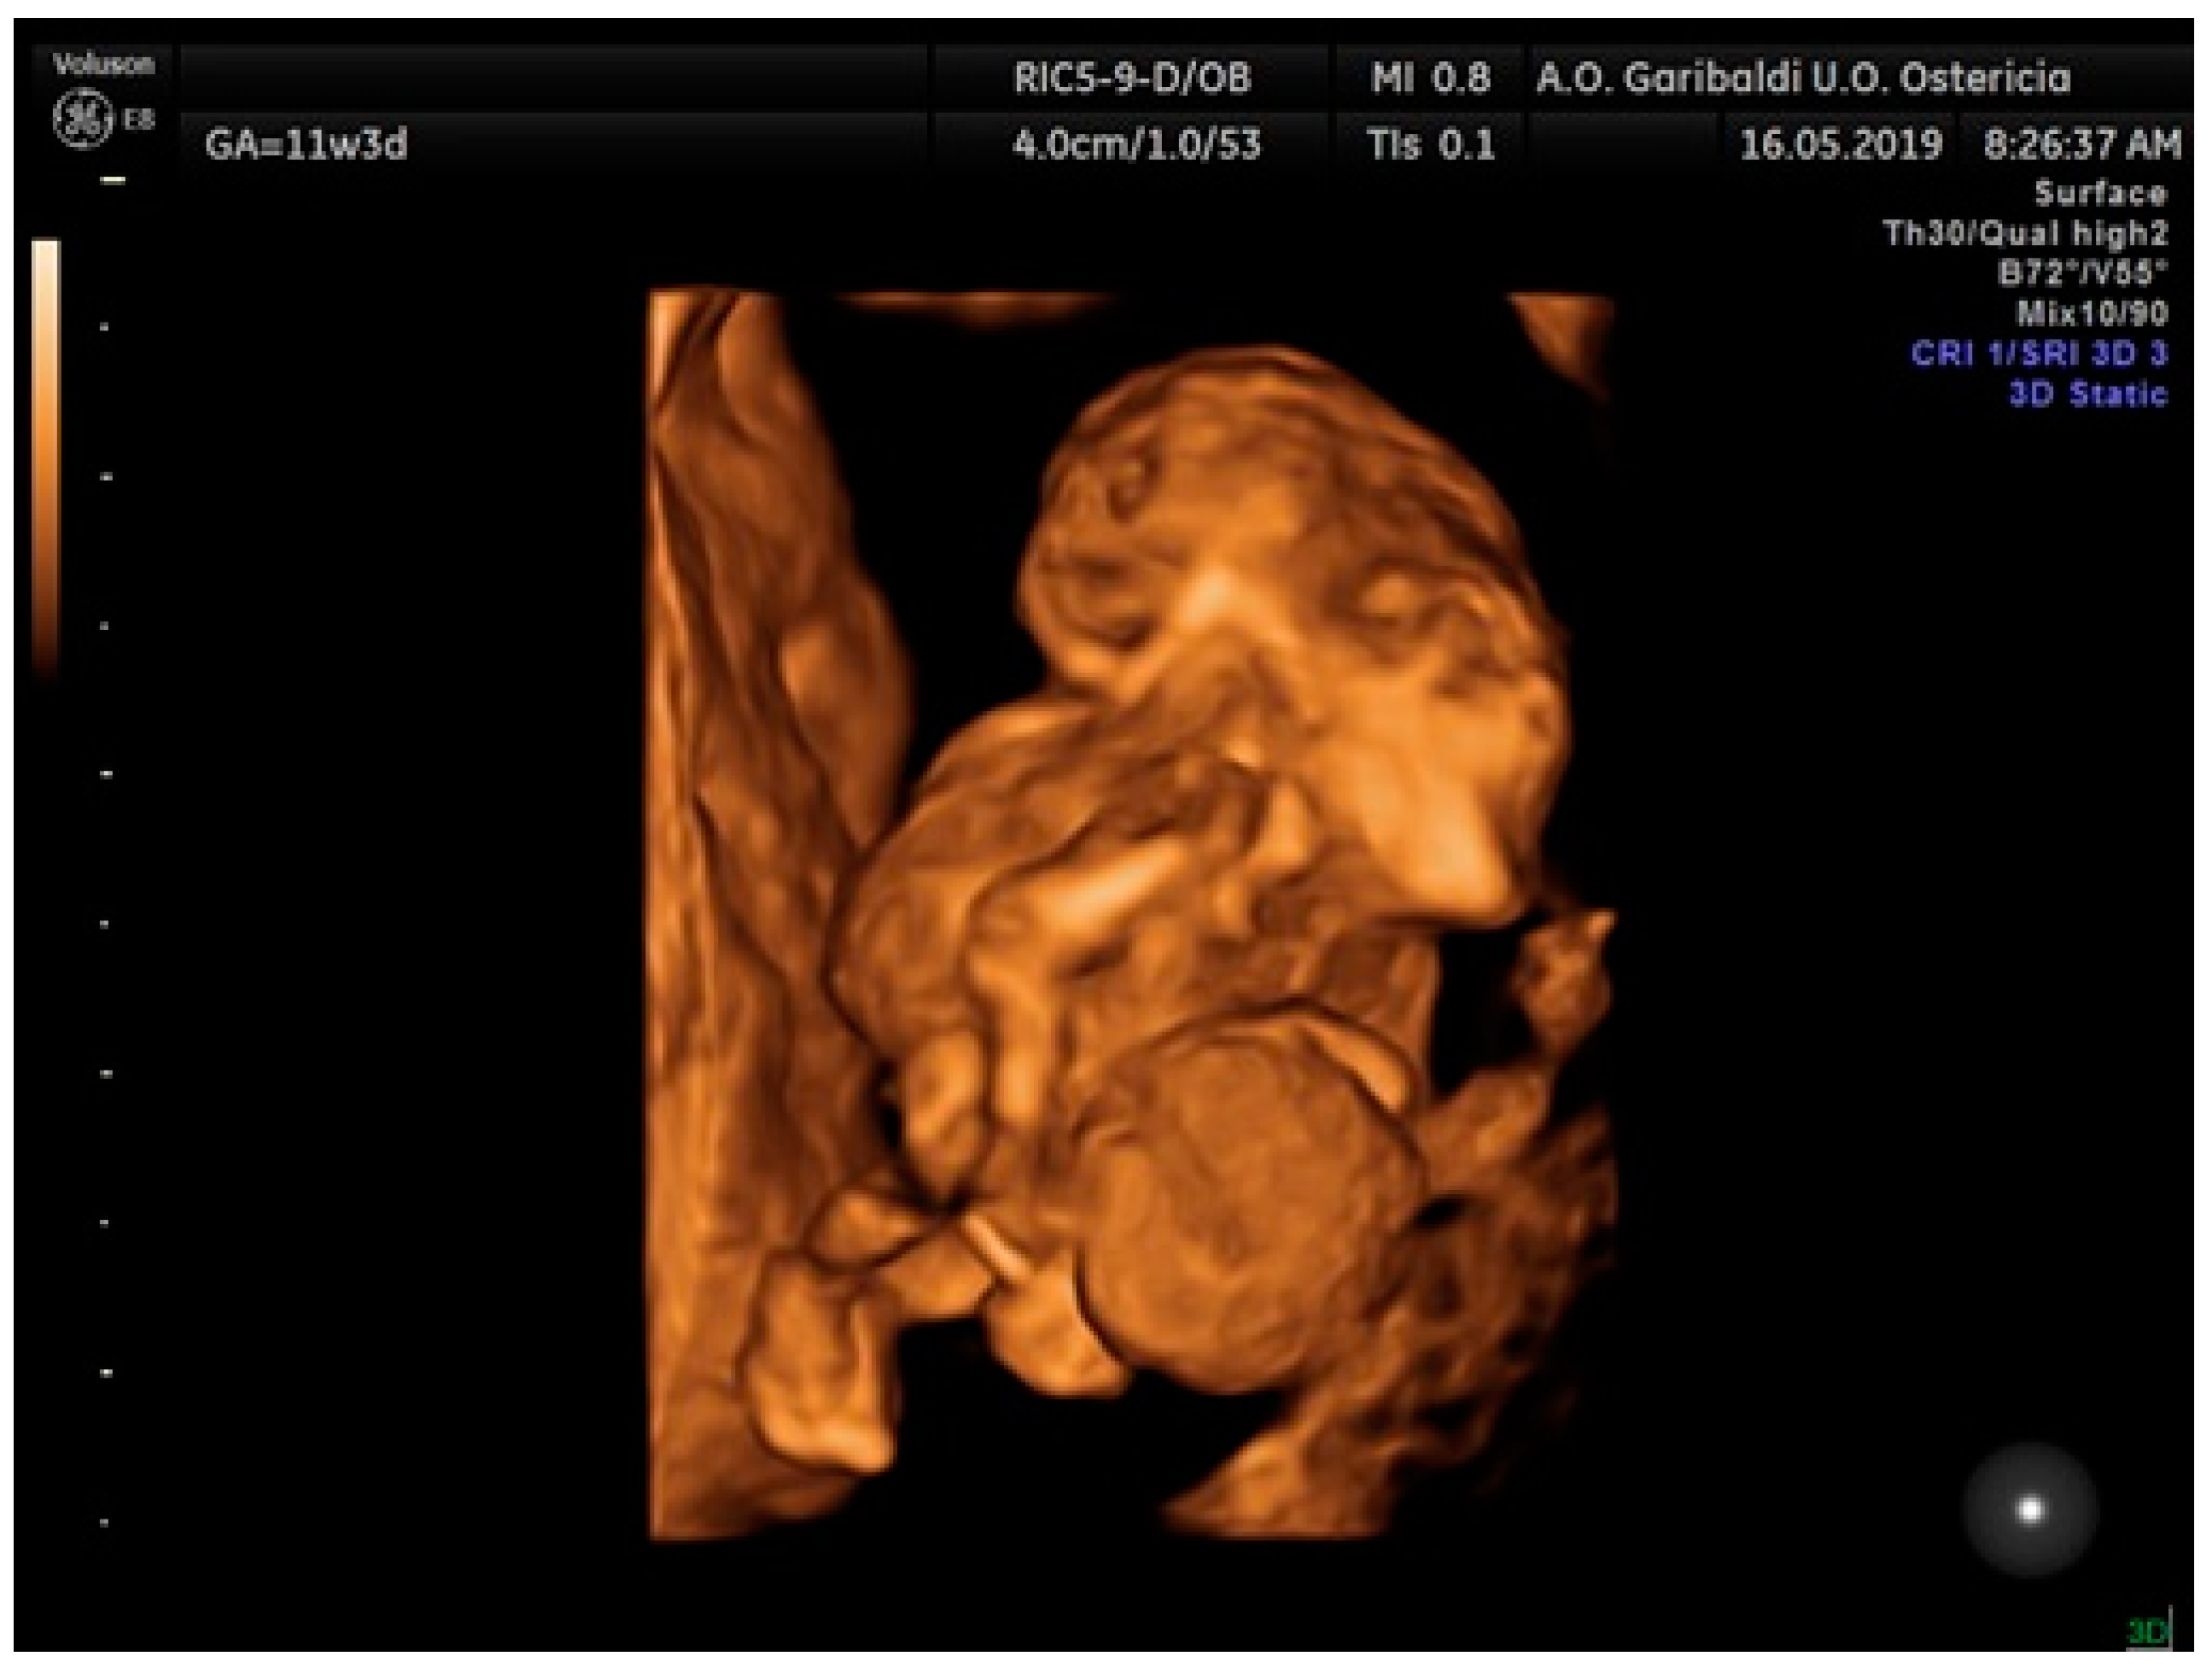

2.1. Case Report 1